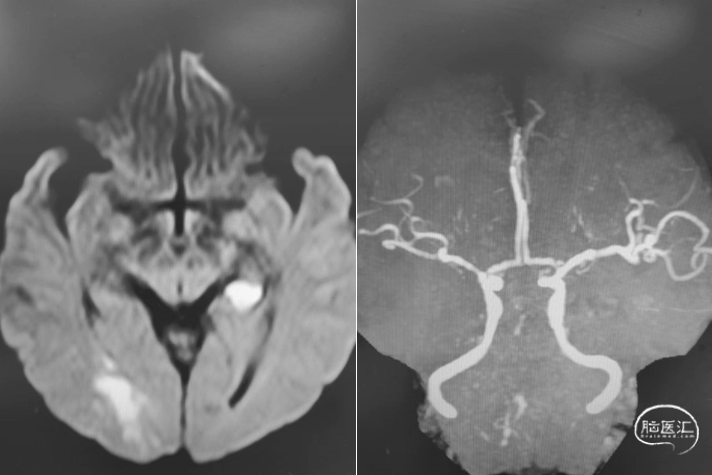

首次DSA 2022.4.9:

重要影像结论DSA:左侧椎动脉闭塞,右侧椎动脉V4段重度狭窄。

内科治疗后仍有新发梗死(2022.8.8):

重要影像结论:桥脑新发亚急性梗死灶,右侧椎动脉重度狭窄。